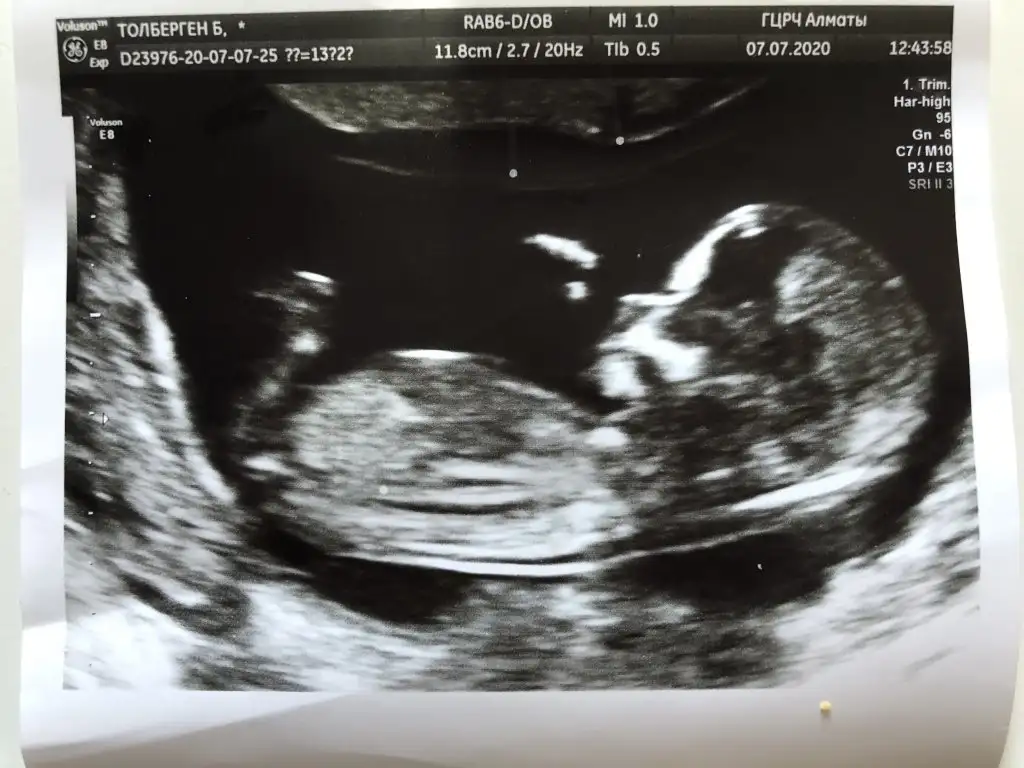

12+3 şuan. Bu seferki usg ler net çıkmadı maalesef ama yine bakabilir misiniz ? Biri usg çıktısı biri ekrandan foto çekimi.

Back